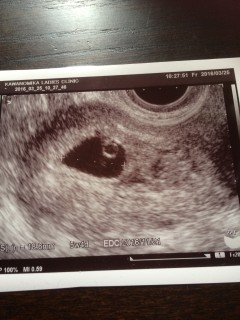

4日前にホーム検査で陽性反応。主人とワクワク産婦人科で初診の時の写真。このサイトで胎のう、胎芽の写真を見ていたから画面に黒い袋と中の白い胎芽を見たとき思わず「いる!」と叫んでしまいました。主人と涙して喜びました。初の妊娠ですが38歳の高齢出産になるので不安もあります。心拍確認、母子手帳をもらいに行きました。頑張ってね、赤ちゃん。

本当は1週間後の検診予定でしたが、妊娠悪阻が酷く、ケトン体が出てしまったのでこの日点滴をして、最後に念の為見てみましょうとの事でエコーをしてもらったら、予想外にもう心拍確認が出来ました。すんごく小さいけどピコピコしてる心臓や、心拍の音を聞いて感動で感極まってしまいました(*^^*) 赤ちゃんは胎嚢19.7mm、胎芽2.5mmでした。どうかこのまますくすく育ってくれますように☆

前回は2年前に胎嚢しか見えず9週で流産してしまいましたがやっと我が家に帰って来てくれました(*^-^*)胎嚢17.4㎜、赤ちゃん3.7㎜、心拍まで確認出来ました☆つわりが食べつわりで結構ツラいですが赤ちゃんが育ってる証拠!と思ってがんばりますo(*⌒―⌒*)o次は2週間後、予定日が確定して母子手帳貰いにいけます。楽しみ♪

前回は胎嚢も見えず化学流産してしまいましたが、生理を一度見送って再び妊娠出来ました。心拍確認できるころまで我慢し、6週になったので受診。すぐに胎嚢が見えて、心臓も動いてますと言っていただけました!胎芽3.2mmとまだまだ小さいですが、順調に育ってくれることを祈るばかりです。

初診では胎嚢、卵黄嚢確認、周期は多分5wくらいとはっきりせず。 そして二回目の健診で赤ちゃんの心拍確認出来ました!!!胎芽3.7㎜!胎嚢13.5㎜!もう嬉しくて嬉しくて笑泣き!順調ですねと先生から言われてニヤニヤが止まらず!大きさ、心拍確認で6wと決定しました。左の卵巣が腫れてるけど排卵?したせいなのでこれは問題無いですと言われて安心です。 一年ほど前に稽留流産を経験しました。あんな辛い思いはもうしたくありません。まだまだ不安だらけですが皆さん頑張りましょう!赤ちゃんを信じましょう!リラックスしてそして強い意志で赤ちゃんと頑張りましょうね!!!

あまり早く行って、胎芽が確認出来ず不安なのも嫌なので、6週目に行きました。先生から3mmで順調と言われました~~(*^o^*)前回8週目で流産したので、次の診察がちょうど8週目なのでまだまだ不安ですが、とりあえず、ちぃさな赤ちゃんが見えた時には感動しました!

初診が6w0dでした! 赤ちゃんが見え隠れして先生が、頑張って心拍をひらってくれました。 「動きたて」とのことで、リズムもまだ不定期でしたが、次の検診まで赤ちゃんの成長を信じて待ちたいと思います! 赤ちゃんは、3.4mmでした。